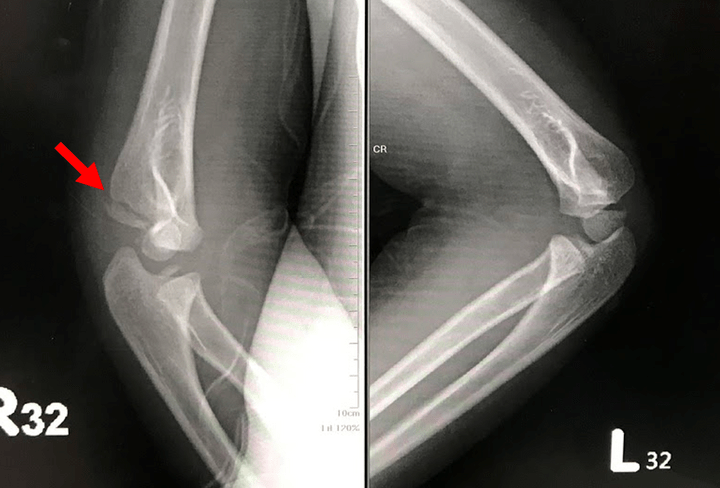

- 癒合不良與變形:如手肘骨折可能出現癒合不良或內翻變形,股骨頭骨折則易發生癒合不良及股骨頭缺血性壞死。